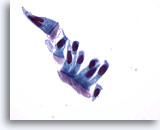

Figure 3

Bronchoalveolar lavage

High magnification of a multinucleated bronchial epithelial cell. Note the terminal bar supporting cilia. 60x

Bronchoalveolar lavage

High magnification of a multinucleated bronchial epithelial cell. Note the terminal bar supporting cilia. 60x

Figure 3

Bronchoalveolar lavage

High magnification of a multinucleated bronchial epithelial cell. Note the terminal bar supporting cilia.

60x

Bronchoalveolar lavage

High magnification of a multinucleated bronchial epithelial cell. Note the terminal bar supporting cilia.

60x